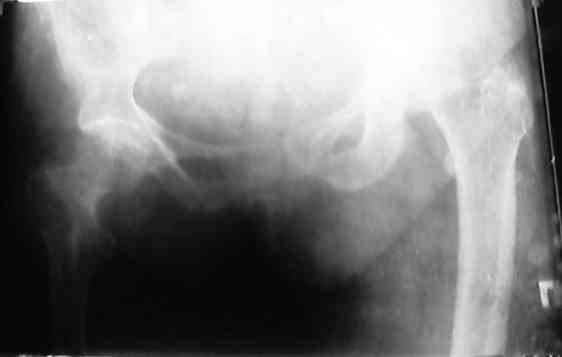

Уважаемые коллеги!помогите, pls определиться с тактикой лечения перелома шейки бедра

Больная 75 лет.Травма 2.10.06. На травмированной конечности - последствия полиомиелита,монопарез конечности, тыльное активное сгибание стопы, активное разгибание к/с-затруднены.пассивные движения в полном объеме. До травмы ходила с палочкой, 7 лет назад (со слов больной) перенесла травму т\б сустава, лечилась на вытяжении 4 мес. Старых снимков, к сожалению, нет. По сердцу - блокада левой ножки пучка Гиса. Точный неврологический диагноз сообщу послезавтраС уважением Д.Б.

По этому снимку можно только гадать, какой перелом, и где он. Надо бы все-таки посмотреть нормальные снимки тазобедренного сустава, обе проекции.

Согласен с А.Н Челноковым, что по этим снимкам можно только гадать какой перелом, хотя судя по возрасту, наверное стоит планировать эндопротезирование, возможен биполяр для уменьшения времени операции и травматичности или тотальное цементноеесли бабушка бодрая

К сожалению качество повторного снимка тоже низкое и отсутствует боковая проекция что бы оценить степень смещения головки вперед-назад

Если смещение минимальное ( по представленому снимку ошущение что перелом шейки без смещения )то рекомендовал бы минимальную операцию по введению CANNULATED SCREWS для фиксации перелома

Кроме того - прошлая травма тазобедренного сустава и лечение вытяжением скорее всего привели к дополнительной деформации и сужению костномозгового канала что конечно осложнит введение протеза на фоне остеопороза